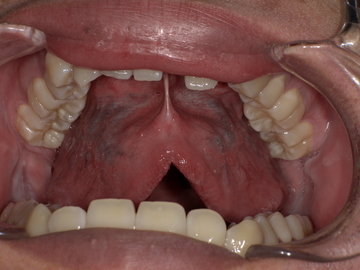

Before

舌小帯が短く、舌先を上あごまで十分に持ち上げることができません。

After

舌小帯形成術後、舌の動きがスムーズになり、上あごにしっかりと届くようになりました。これにより、発音に必要な舌の動きが改善されます。